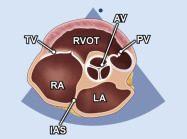

| 2.8. Mặt cắt trục ngắn cạnh ức (ngang mức các đại động mạch) khu trú vào van động mạch chủ |

||||||||

|

|

Cửa sổ siêu âm cạnh ức

Mặt cắt trục ngắn cạnh ức Xoay đầu dò 90O từ mặt cắt trục dài cạnh ức và ngửa đầu dò để ghi hình rõ các cấu trúc giải phẫu ngang mức động mạch chủ |

Van động mạch chủ (AV)

Nhĩ trái (LA) Nhĩ phải (RA) Van ba lá (TV) Đường ra thất phải (RVOT) Van động mạch phổi (PV) Vách liên nhĩ (IAS) |

|||||